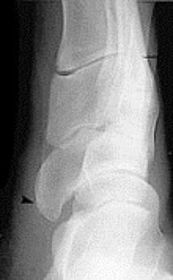

What disease is this? What does the arrow indicate? | Rheumatoid arthritis. Arrow = Bone erosion secondary to inflammation of retrocalcaneal bursa. |